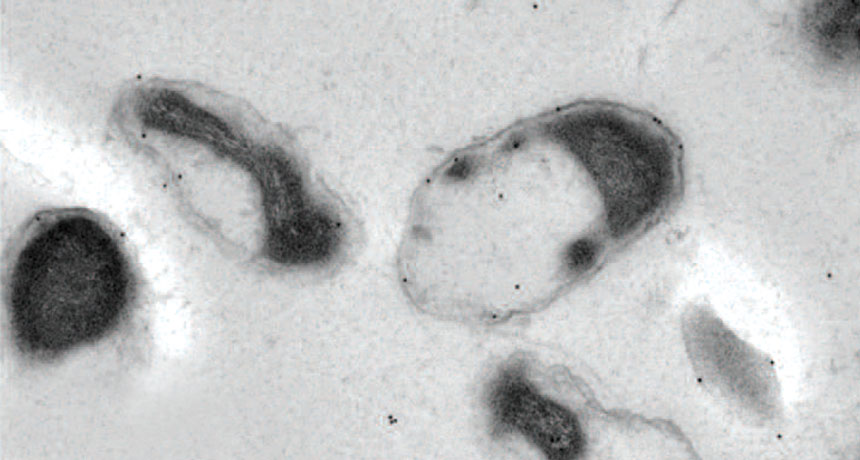

GUT GUARDIAN  A friendly gut bacterium called Akkermansia muciniphila (shown) may help protect against type 2 diabetes. Those bacteria are lost with aging, setting the stage for the disease.

N. Ottman et al/Frontiers in Microbiology 2016